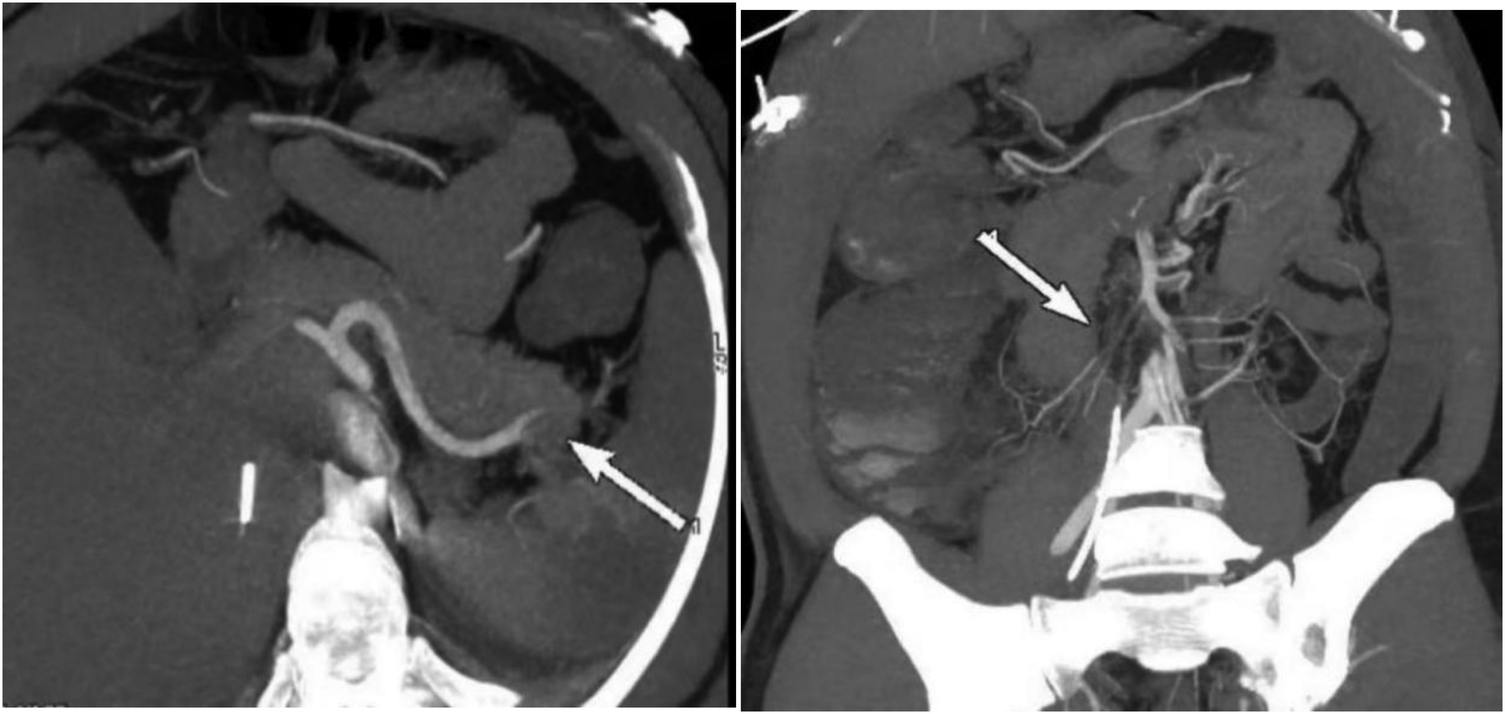

On the 11th day of hospitalization (PCI and IABP) the patient's abdominal pain did not improve, and urine output significantly decreased. The patient's abdominal circumference (95 cm) and intra-abdominal pressure (7.5 cmH2O) were both increasing on the 12th day, ALT reached its peak (154 U/L), and the levels of blood lipase and amylase were a slight increase and lipase exceeded the normal upper limit, so abdominal vascular computed tomography angiography (CTA) was performed and revealed multiple thromboses involving the celiac trunk, upper and lower mesenteric arteries, splenic artery, bilateral renal arteries, left inferior gluteal artery, as well as branches of the proper hepatic artery. These thrombotic events led to secondary infarction of the spleen and bilateral kidneys. Additionally, gas accumulation in the intestinal wall of the ascending colon and suspected ischemic necrosis of the distal ileal intestinal wall were noted, indicating ischemic bowel involvement (Figure 1).

Figure 1

Preoperative CTA showed an acute completely embolic occlusion of arteria mesenterica superior and splenic artery (arrow).